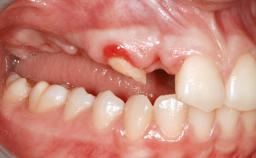

A 46-year-old woman was referred for treatment whose main complaints were mobility of her fixed partial dentures (right maxilla and left mandible) and periodontal bleeding during function. She also reported having taken systemic antibiotics to treat recurrent swelling in the area of the upper left molars. The patient had not seen a dentist for at least 2 years. She did not smoke and had no history of major systemic disease other than two minor orthopedic procedures some years back. The first-visit examination revealed poor plaque control, tooth mobility, periodontal disease, and a residual dentition widely associated with deep periodontal pockets.

Infection at Implant Site None Chronic Acute

Soft Tissue Anatomy Intact Defective

Bone Volume Horizontally and vertically sufficient Horizontally deficient Deficient vertically or deficient vertically AND horizontally

Bone Volume Deficient vertically or deficient vertically AND horizontally